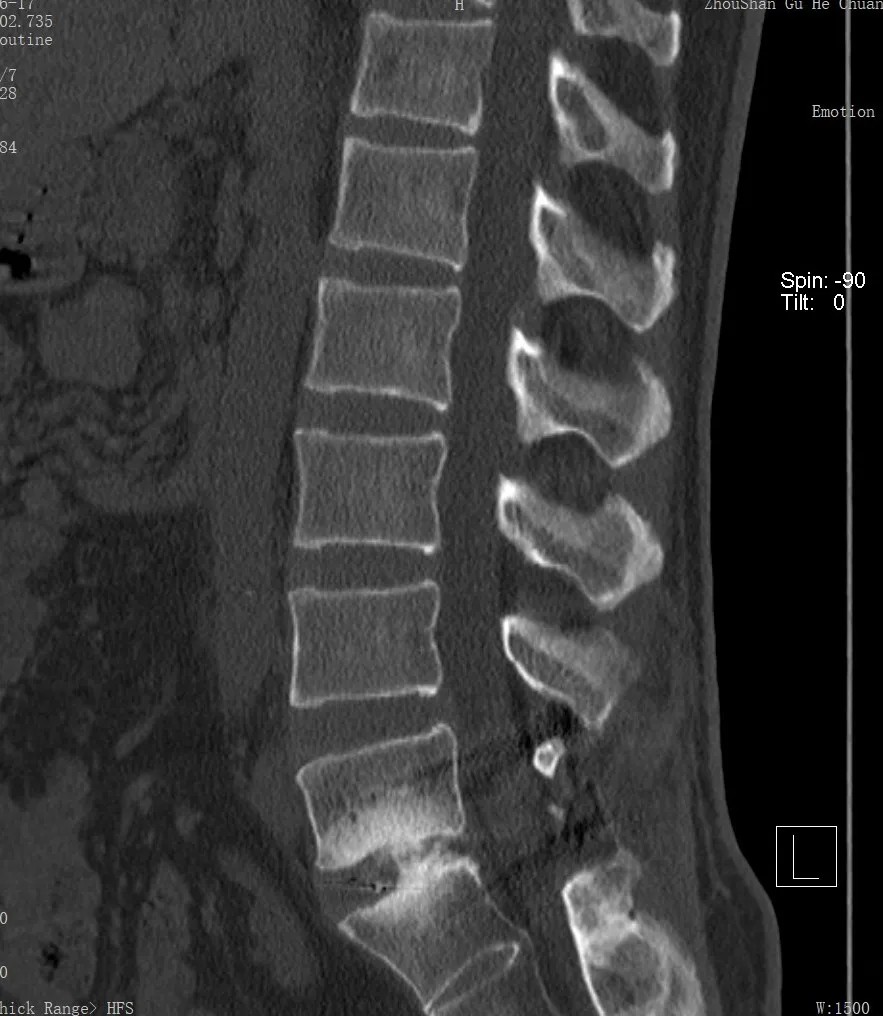

我院脊柱科、微創(chuàng)治療中心專家團(tuán)隊(duì)聯(lián)合內(nèi)科監(jiān)護(hù)團(tuán)隊(duì)進(jìn)行多學(xué)科會(huì)診,通過詳盡的病史詢問、體格檢查及相關(guān)影像檢查,為患者進(jìn)行了精準(zhǔn)的診斷。

針對患者復(fù)雜的病情及二次翻修手術(shù)的情況,我院專家團(tuán)隊(duì)?wèi){借豐富的經(jīng)驗(yàn)、專業(yè)的技術(shù)、密切的配合,為患者在蔡司TIVATO 700手術(shù)顯微鏡下實(shí)施了腰椎融合術(shù)后翻修、融合內(nèi)固定微創(chuàng)手術(shù)。